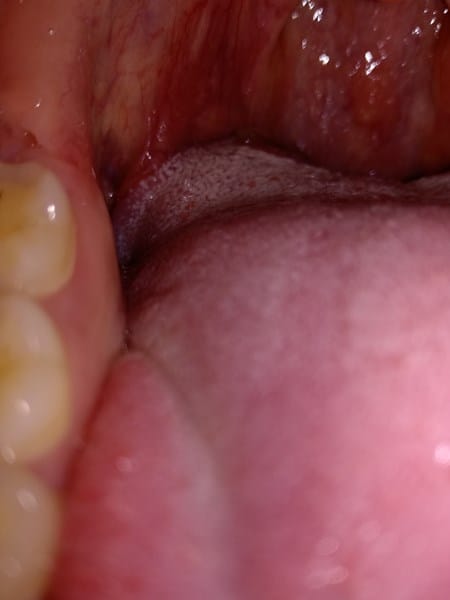

I. Hola Gemma, creo, según estoy leyendo, que podría tratarse de un cuadro de reflujo intestinal. (Acidez estomacal), La placa placa de color blanquecino por lo visto es conocida como 'saburra'.

Un doctor online comentó lo siguiente:

"**SABURRA " Ese es el nombre de la capa blanca que cubre la zona posterior de tu lengua, es frecuente que sea abundante y gruesa en pacientes con reflujo gastroesofágico. Una de las formas de disminuirla es llevando una dieta sana sin excesos de grasas ni frituras, no comer nada dos horas antes de acostarse, evitar los aderezos como Ketchup y Mayo. Las infusiones de manzanilla caliente después de almuerzo son beneficiosas en resumen, dieta sana sin excesos de grasas, frituras y fibras como la de la cebolla o el ollejo de las legumbres, realizar deportes que fortalecen tu musculatura abdominal, tratar que los alimentos tengan una constitución más pastosa que liquida.**

En ignorancia pienso que podrías solicitar un cultivo de la zona (muestra de tejido), en el médico de cabecera o especialista habitual, de esta forma se analiza un trocito de la placa para averiguar si existe una infección y de qué tipo. Creo que aquí podemos ver más información. Mucho ánimo.